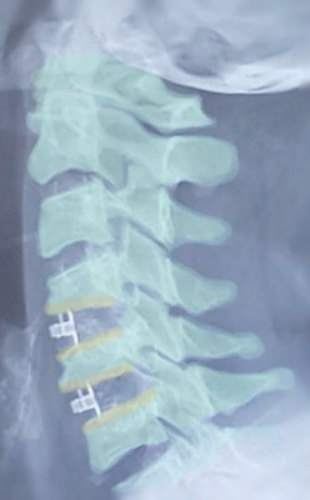

یکی دیگر از شکایات بسیار رایج نزد بیماران، درد گردن است که گاها با انتشار به شانه ها و یا بازو و ساعد و انگشتان دست نیز همراه بوده و متاسفانه در بعضی موارد شدت درد غیر قابل تحمل میباشد.

در مواردیکه علت درد گردن مشخصا پارگی دیسک گردنی و یا تنگی واضح کانال نخاعی یا مجاری اطراف آن و یا استخوانی شدن لیگامانهای گردن باشد، درمان جراحی میتواند موجب کاهش درد، پیشگیری از نقص عضو ناشی از اثرات فشاری بروی نخاع و عصبها، و بهبودی چشمگیر کیفیت زندگی بیمار شود.

با توجه به ارتباط نزدیک دیسکها و مهره های گردنی با نخاع، و همچنین ابعاد نسبی کانال نخاعی و خود نخاع گردنی و قابلیتهای حرکتی ناحیه گردن، بیماریهای این ناحیه بمراتب حساستر از ناحیه کمر بوده و توجه و پیگیری بیشتری را از جانب بیمار میطلبد.

در جراحیهای ستون مهره ها، در مواردیکه ثبات ستون مهره ها، چه بدلیل بیماری مزمن و چه بدلیل شکستگیها و ضربه ها، در حد رضایت بخش نباشد، از تکنیکهای فیوژن ستون مهره ها، یا بعبارت دیگر استفاده از پروتزهای تیتانیومی برای استحکام بخشیدن به ستون مهره ها استفاده میشود.